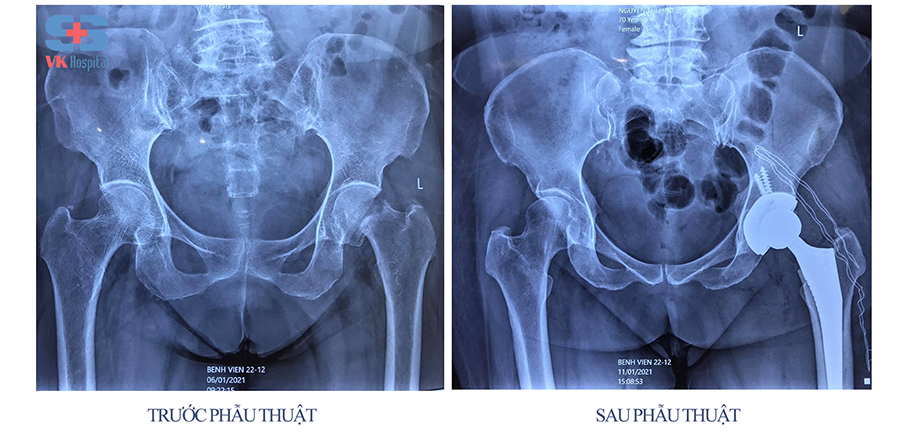

Các bác sĩ Bệnh viện 22-12 mổ thay khớp háng cho bệnh nhân

Bệnh nhân nên được chuyển sớm tới bác sĩ phẫu thuật chấn thương chỉnh hình. Do phần lớn các trường hợp gãy cổ xương đùi đều cần can thiệp phẫu thuật. Thời điểm tiến hành mổ thường được chỉ định trong vài ngày sau chấn thương. Phẫu thuật giúp người bệnh vận động sớm, ngăn ngừa những biến chứng do nằm lâu, bất động lâu.

Tình trạng này có gây tổn thương mạch máu không cũng góp phần xác định phương pháp phẫu thuật nào được thực hiện. Có 2 phương pháp thường được chỉ định tùy thuộc loại gãy xương và tình trạng sức khỏe của người bệnh, cụ thể:

- Kết hợp xương: Phương pháp này sử dụng đinh, vít, nẹp… để cố định ổ gãy, hỗ trợ liền xương. Ưu điểm là cố định vững, vận động sớm sau mổ, ngăn ngừa các biến chứng bất động lâu và liền xương khá cao, có thể bảo tồn được chỏm.

- Thay khớp háng: